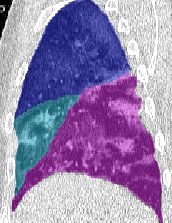

Lobar Segmentation

Lobar segmentation results for the proposed method and PTK are shown in Figure 5 for right lungs and Figure 6 for left lungs. For each image in the COVID-19 dataset (133 images in total), the lobar segmentation result was used to extract the amount of poor aeration () and consolidation () in each lobe. Common phenotypes of COVID-19 affected lungs were identified by hierarchical clustering over the fraction of poorly aerated and consolidated tissue in each lobe. Dendrographic analysis in Figure 7 reveals four primary clusters of patients that were identified by the hierarchical clustering: (a) mild loss of aeration primarily in the two lower lobes without consolidation; (b) moderate loss of aeration focused in the two lower lobes with or without consolidation in lower lobes; (c) severe loss of aeration throughout all lobes with or without consolidation; and (d) severe loss of aeration and consolidation throughout all lobes.

| CT Image | PTK | Proposed |